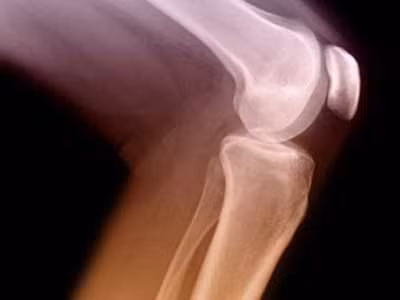

Đau khớp gối là một triệu chứng của nhiều bệnh khớp khác nhau như chấn thương khớp gối, viêm khớp gối, thoái hóa khớp… Dưới đây là một số cách điều trị triệu chứng đau khớp gối.

Bạn bị viêm đau khớp gối và thường nghe thấy tiếng kêu lạo xạo, viễn cảnh về một khớp gối mới được làm kim loại và nhựa dẻo dường như rất hấp dẫn. Tuy nhiên thực tế có đúng như mong đợi?